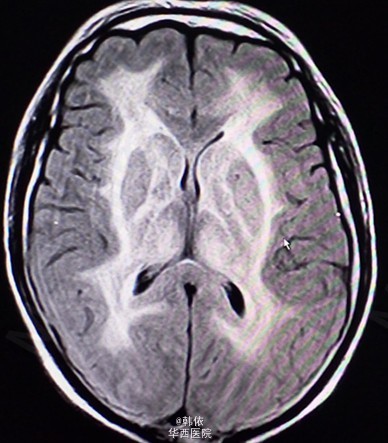

原创:青年男性,因“反复突发意识障碍1+月”入院,1+月前,患者感冒后突发意识障碍,呼之不应,随之出现四肢抽搐,双上肢屈曲、抽搐,双下肢强直,双眼向上凝视,牙关紧闭,小便失禁,无口吐白沫等,持续10+秒后意识恢复,不能回忆,急诊入当地医院治疗,行脑脊液、头部增强MRI等检查,考虑“痫性发作,病毒性脑膜炎”给予降颅内压、抗病毒等治疗,患者住院过程中出现一次右下肢抽动及多次小便失禁,治疗过程中感头部昏沉感,呈持续性,并出现饮水呛咳,治疗效果欠佳。既往患有高血压2+年,未治疗。长期农药接触史2+年。查体:神清,对答切题,高级神经活动正常,双瞳孔等大等圆3mm,对光反射灵敏。四肢肌力肌张力正常,左侧病理征(+),右侧病理征(-),余无特殊。辅助检查:头部MRI示:双侧基底节、双侧丘脑、脑干、双侧小脑及双侧侧脑室旁、双侧半卵圆中心对称性信号异常,考虑中毒性、代谢性疾患可能(见下图)。